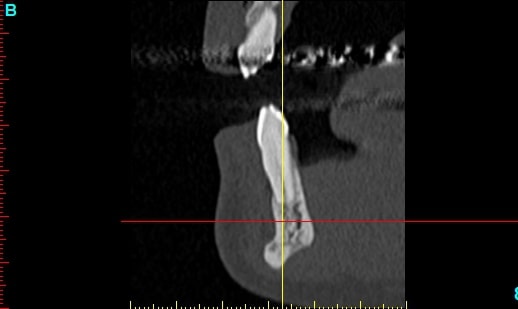

Patiente 58 ans à eu une chirurgie à visée esthétique et "fonctionnelle" adressée pour détartrage en urgence...je ne suis pas spécialiste mais je trouve que la greffe mentonnière est très bof

lésion apicale sur 42 risque de contamination sur la vis en regard..

Nous sommes d'accord pour la chirurgie mais secteur 4 il y a 2mm être là plastie et la mdble, ça ne me fais pas rêver

Nous sommes d'accord pour la genioplastie je me suis mal exprimé ce qui m'inquiète c'est la proximité de la greffe, pardon genioplastie et de l'infection de 42, d'une part et la mauvaise liaison de la genioplastie secteur 4, mais je suis peut-être pessimiste.

Plusieurs points: les vis de 15mm x 2mm qui transfixent c'est pas top, une seule plaque, qui plus est non réglable de chaque côté, c'est encore moins top. C'est une plaque de fracture.

En mandibulaire gauche c'est quoi ce fil d'osteosynthese? Un troisième fragment? En laissant l'apex de la 48 pile sur le trait d'osteotomie, je dis chapeau.

Pour la lésion de 42, ca peut être lié à la genio. Forage hasardeux? Mais je vote plus pour une lésion endo/paro